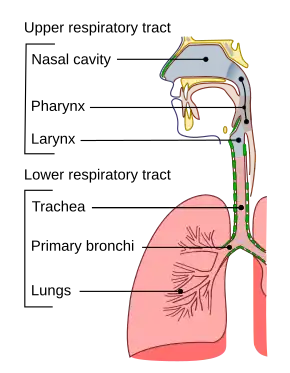

Choking occurs when a foreign body blocks the airway.[17][18] This obstruction can be located in the pharynx, the larynx, trachea, or lower respiratory tract.[19] The blockage can be either partial (insufficient air passes through to the lungs) or complete (complete blockage of airflow).[19]